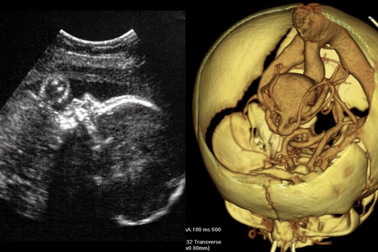

Phẫu thuật thành công một bào thai mắc dị tật hiếm ở nãoMột bào thai còn trong bụng mẹ mắc dị tật hiếm gặp được các bác sĩ phẫu thuật não để sửa chữa một mạch máu bị dị dạng và em bé đã ra đời khỏe mạnh.